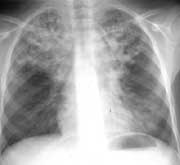

В 1998 г. девочка консультируется в клинике "Гроссхарден" (Мюнхен, Германия), где проводится интенсивная терапия с применением больших доз антибиотиков, в результате чего бронхоэктазы очистились (Рис. 2), микрофлора нормализовалась.

Рис. 2. Положительная динамика после интенсивного консервативного лечения.